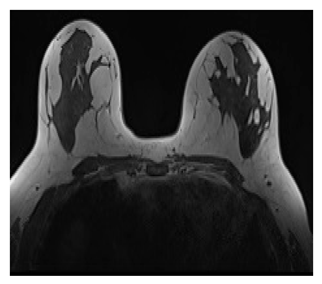

| MRI | High Spatial Resolution | High sensitivity (detecting invasive cancer) Identify undetected malignancies by mammography |

Expensive, prone to false positives. Requires validation. Low specificity |

![]() |

- Detecting magnificence in higher rates: Comparing to mammography for example, MRI said to have a sensitivity rate of 90% comparing to 60% in the best case of MG, increasing the true detection rate in average of 16-30%.

- Detecting malignancies in earlier stages:

- Cancers with tiny sizes most of the time are not detected when using MG only, on the other hand using MRI significantly enhances the rates of detection at these stages.

- Decreasing mortalities by increasing survival rates: